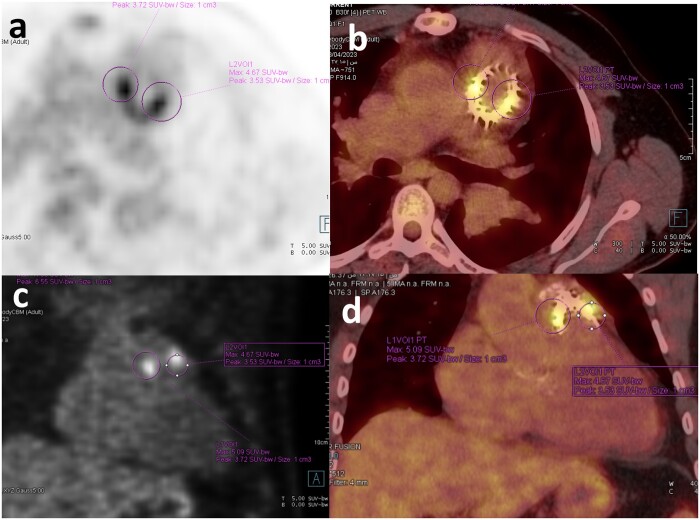

Q fever is an epidemic disease caused by the Coxiella burnetii infection. It can manifest clinically as an acute or chronic disease, with chronic infections being more common. Q fever endocarditis is the most common manifestation of chronic infection and usually occurs in patients with previous valvular heart disease like in our present study, a case of Q fever endocarditis that occurred in background of tetralogy of Fallot surgical repair. However, Q fever endocarditis is difficult to diagnose clinically and may lead to very serious or even life-threatening outcomes if not diagnosed promptly. In the present study, accurate diagnosis and treatment were achieved by 18F-FDG PET/CT combined with detection of the Q fever serological antibodies.